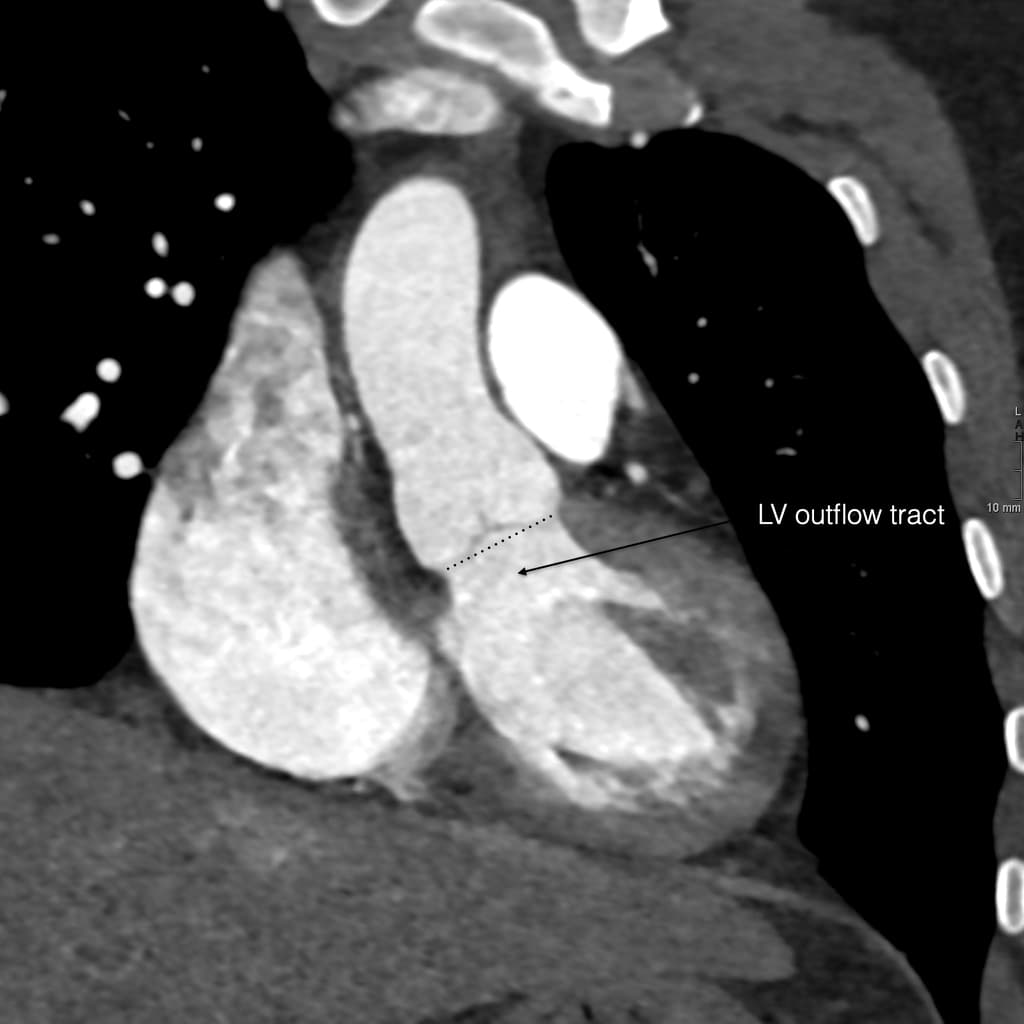

- Hình ảnh CTA mặt phẳng vành chếch (Oblique coronal CTA) của gốc động mạch chủ (aortic root) hiển thị các cấu trúc giải phẫu liên quan.

- Gốc động mạch chủ (aortic root) nằm giữa vòng van động mạch chủ (aortic annulus) — là điểm nối giữa đường ra của thất trái (outflow tract of the left ventricle) và van động mạch chủ (aortic valve) — và chỗ nối xoang - ống (sinotubular junction) — nơi động mạch chủ lên (ascending aorta) bắt đầu.

Gốc động mạch chủ là một vùng giải phẫu phức tạp nằm giữa đường ra thất trái và động mạch chủ lên. Nó bao gồm vòng van động mạch chủ (điểm nối giữa đường ra và van), các xoang Valsalva và chỗ nối xoang - ống (nơi động mạch chủ lên bắt đầu). Đánh giá chính xác các cấu trúc này trên chụp cắt lớp vi tính mạch máu (CTA) là rất quan trọng để lập kế hoạch trước thủ thuật thay van động mạch chủ qua ống thông (TAVI), vì nó đảm bảo lựa chọn kích thước van nhân tạo chính xác và giúp giảm thiểu các biến chứng trong thủ thuật.